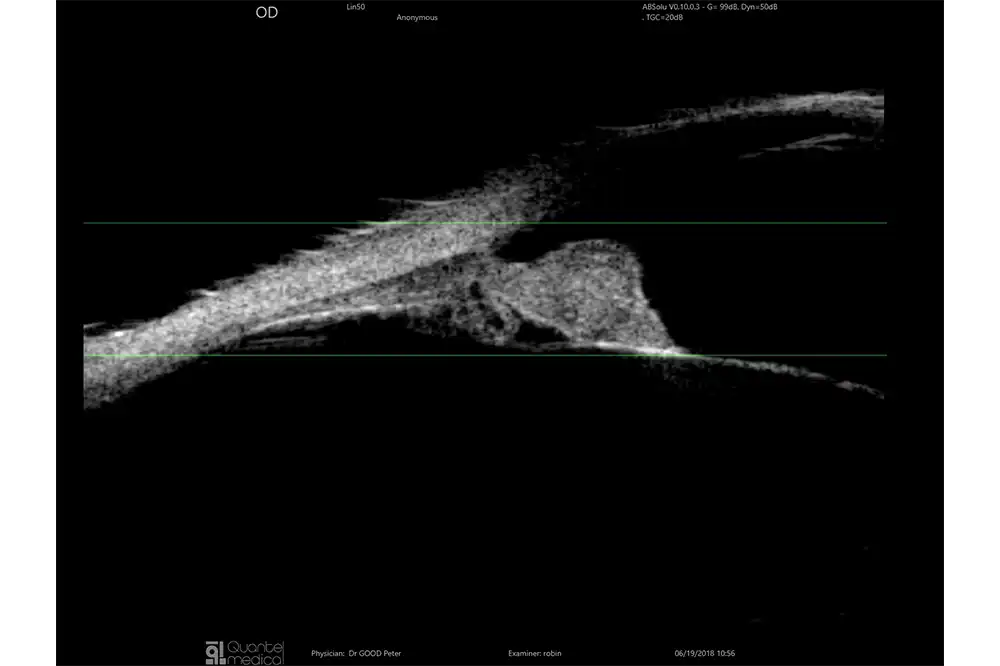

De sondes B15, B20-5A en UBM zijn uitgerust met een IMUv®-bewegingssensor die essentiële real-time informatie biedt, zoals:

- De positie van de sonde op het oog

- De visualisatie van het waargenomen gebied

Dit helpt de operator om onderzoeksgebieden eenvoudiger en sneller te identificeren. Deze technologie is gepatenteerd en exclusief voor Quantel Medical.

- Nieuwe UBM technologie die verschillende beeldmodi mogelijk maakt.

- Exclusieve IMUv™-bewegingssensor maakt het mogelijk om de ultrasone bundel in real-time in het oogdiagram te lokaliseren.